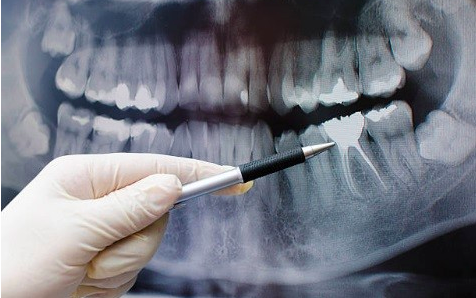

L’endodonzia è la specialità che si occupa del trattamento del canale radicolare ed è la base dell’odontoiatria, perché la vita del dente dipende principalmente dalla correttezza di questo trattamento.

Il trattamento del canale consiste nella rimozione del tessuto nervoso vascolare (del “nervo”) dai canali radicolari, seguito dalla pulizia, dall’ampliamento e dalla sterilizzazione di questi canali e quindi dalla loro ostruzione. L’otturazione del canale rappresenta l’ultimo stadio del trattamento endodontico e consiste nel sigillare le radici con materiali speciali, che prevengono le infezioni.

Il dente ha un tessuto vascolare e nervoso (nervo) all’interno dei canali radicolari, che garantisce l’apporto di nutrienti. Quando si verificano infiammazioni o infezioni di questo tessuto, è necessario rimuoverlo. Il trattamento del canale consiste nel rimuovere il nervo dai canali radicolari, seguito dal riempimento (riempimento) con materiali speciali, che assicurano la tenuta e prevengono le infezioni. Inizialmente, questo trattamento viene eseguito per rimuovere il dolore e curare o prevenire l’infezione. L’obiettivo finale è quello di mantenere la funzionalità del dente.